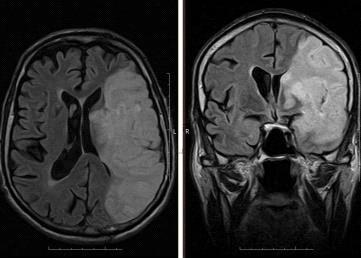

Примеры снимков представлены на рисунке 3.2 и 3.3.

Рис. 3.2 - ЛСМА (инсульт)

Рис. 3.3 - Тазобедренные суставы (норма)